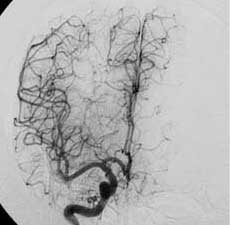

一、颅内动脉瘤

----对颅内动脉瘤的介入治疗主要分为载瘤动脉闭塞和选择性动脉瘤栓塞两种。对于颈内动脉岩部或海绵窦段以及后循环的梭形或宽颈动脉瘤,在代偿试验良好的情况下,可以闭塞载瘤动脉。半年后动脉瘤可逐渐皱缩吸收,明显减少压迫效应。如侧支循环代偿不足,则应先行颅内外动脉架桥。选择性动脉瘤内栓塞主要适用于瘤颈清楚、后循环动脉瘤、多次SAH、HH分级偏高,有血管痉挛或手术风险较大的患者。 近年来,由于显微导管和栓塞材料的可控制研制,使得颅内动脉瘤的血管内栓塞治疗越来越普遍。在欧洲,几乎占所有治疗动脉瘤的80%。栓塞材料主要由Guglielmi等发明的电解脱铂金弹簧圈(GDC)为先导,使动脉瘤的栓塞可以控制释放弹簧圈,进出自由,大大增加了安全性和载瘤动脉的保留。经栓塞后的患者通常2~3天即可出院。尤其对于后循环或巨大动脉瘤等手术难以接近或无法夹闭的动脉瘤,栓塞更是独辟蹊径,是手术治疗盲区的重要补充。